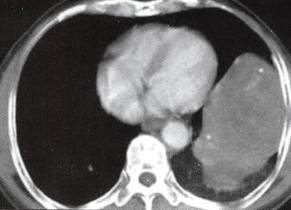

图1胸膜孤立性纤维瘤

A

B

C

D

A.B.CT平扫示左中下胸巨大肿块,宽基底与胸壁相连,内见斑片状钙化;

C~F.CT增强扫描肿块内缘肺门侧见一血管蒂样结构与纵隔相连,中度不均匀强化,内见匍行、紊乱的血管影,肿块中度均匀强化;